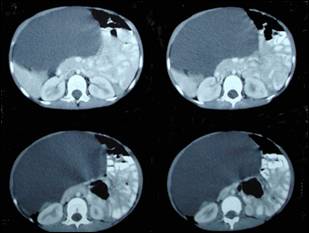

Image 2: CT scan showing

position of the cyst just beneath the anterior abdominal wall with compression

of the adjacent viscera